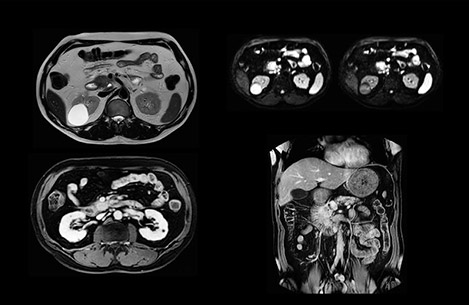

“We include mDIXON for the dynamic sequences because of the robust and homogeneous fat suppression we get with that. We had been using eTHRIVE, but we are now quite happy with mDIXON. Sometimes we use a medication to calm the bowels, to further improve the image quality.”

“We acquire one transversal high resolution T2-weighted sequence with 3 mm slice thickness, for example for pancreas or liver lesions. Then we also add a T2 fat suppressed MultiVane XD SPIR sequence. We perform these two routinely in our liver imaging. We use high dS SENSE factors to significantly shorten scan times to 2-4 minutes, which can improve our protocol; it’s a very robust scan.”